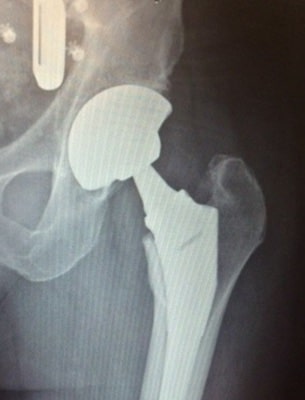

A hip replacement is a surgical procedure that replaces the abnormal or worn surfaces of the hip joint. The surgery is typically performed to reduce hip pain from arthritis or to repair a fractured hip. In this procedure, Dr. Moore will remove the diseased, not well-functioning hip joint using a titanium/tantalum porous metal implants and high grade polyethylene of ceramic or metal interface. It is typical that your hip replacement would not require the use of bone cement, which is only used in rare cases.

The process of replacing a hip involves removal of the diseased femoral head. Removal of the femoral head allows Dr Moore access and visualization of the diseased acetabulum. Dr Moore will use specialized acetabular reamers to remove the diseased acetabular bone sequentially.

Once this is accomplished he will replace the disease and removed cartilage with a trabecular metal acetabular component in which your bone will grow into the porous metal component. A high grade polyethylene liner is then placed in the metal component and locked into place. At this point, Dr Moore will address the top or proximal end of the femur/the end the femoral head was removed from. He will again and sequentially use specialized femoral broaches to create an envelope that matches the femoral implant.

The implant that Dr Moore uses in the femur also has porous metal pads that your native bone will grow into. Once this part of the procedure is completed Dr Moore and his surgical team begin trialing femoral head sizes and lengths ensuring the most stable hip and equal leg lengths. Dr Moore will choose the appropriate size femoral head which will be either ceramic or titanium. Dr Moore’s patients are up and walking the day of surgery while putting full weight on their operative leg. Modern total hip replacement implants last 25-30 years.